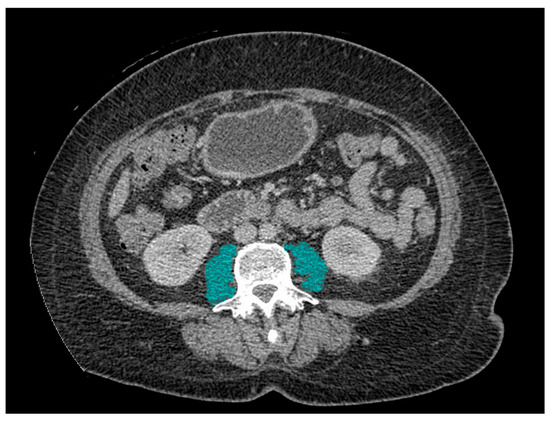

2.1. Definition of Sarcopenia